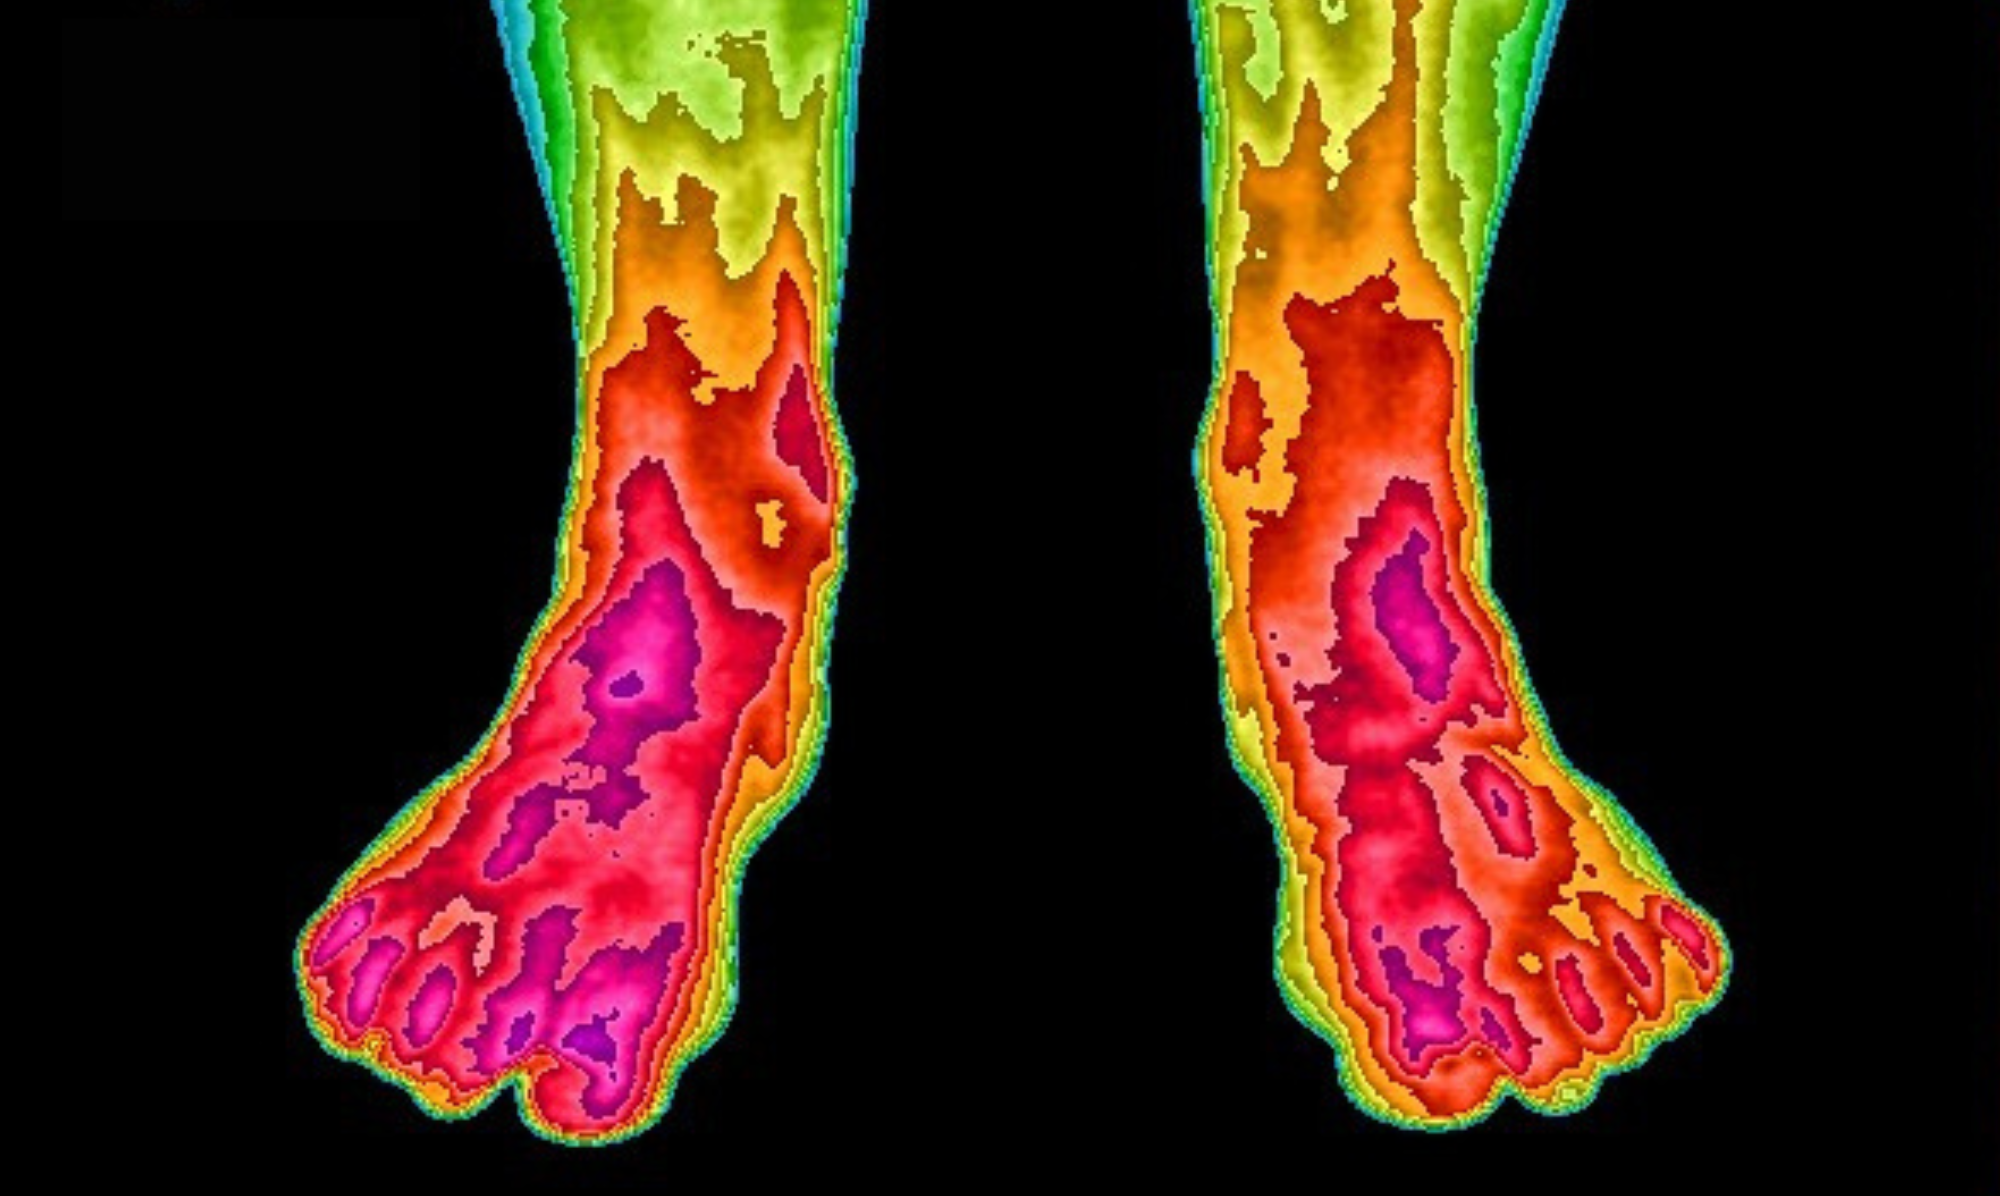

Earthing has been involved with more than 26 scientific studies showing how being grounded positively influences our bodies. These infrared images are an evaluation tool showing changes in blood flow before and after grounding for two weeks on our Ground Therapy Mattress Cover. Before grounding, circulation was almost non-existent in the toes. After grounding, normal circulation has been restored. This is one small example of the studies that have been done.